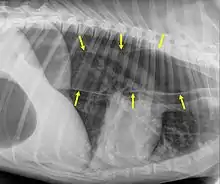

Megaesophagus, also known as esophageal dilatation, is a disorder of the esophagus in humans and other mammals, whereby the esophagus becomes abnormally enlarged. Megaesophagus may be caused by any disease which causes the muscles of the esophagus to fail to properly propel food and liquid from the mouth into the stomach (that is, a failure of peristalsis). Food can become lodged in the flaccid esophagus, where it may decay, be regurgitated, or maybe inhaled into the lungs (leading to aspiration pneumonia).[1]